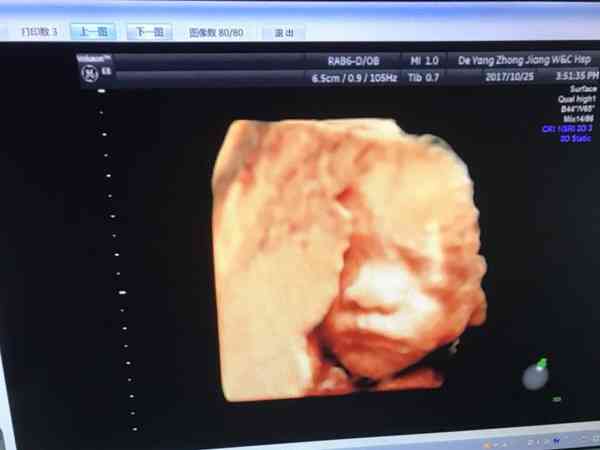

孕婦四維被誤診的真實案例是存在的例如26周排畸誤診足內翻,26週四維排畸寶寶不配合,不讓看,醫生建議活動40分鐘後,回來繼續做,第二次是看不到嘴, 心臟其它正常,看著有隻腳彆扭,後來複查嘴巴正常,但是左腳看著彆扭,懷疑馬蹄內翻足畸形,其它一切正常,現在寶寶已生,很健康。當然不止這麼一個案例所以要做四維彩超的時候,去正規大醫院,比較有保障。孕婦四維被誤診的真實案例是存在的,四維彩超雖然準確性比較高能達到95%以上,但是也不是一定準確的,畢竟四維彩超除了依靠裝置外,還要依賴醫生的細心和經驗,所以,四維彩超也是有誤診的可能的,而現實生活中也有不少真實的誤診案例存在,下面一起來看幾起四維被誤診的真實案例:

26週四維排畸寶寶不配合,不讓看,醫生建議活動40分鐘後,回來繼續做,第二次是看不到嘴, 心臟其它正常,看著有隻腳彆扭,後來複查嘴巴正常,但是左腳看著彆扭,懷疑馬蹄內翻足畸形,其它一切正常,現在寶寶已生,很健康。

24w四維時說房間隔缺損5.7mm,後來28w去另外一家醫院做的心臟彩超,一點問題也沒有,要不就是寶寶自己長好的,要不就是當時做四維醫院的誤診。

四維時候說寶寶右腳腳內翻,後來到成都又做了一次四維彩超,翻盤了,寶寶健健康康的。

雖然有誤診的可能,但是四維彩超誤診機率並不大大,特別是在24-26週四維彩超的最佳時間內進行檢查,誤診的可能性性更是小。